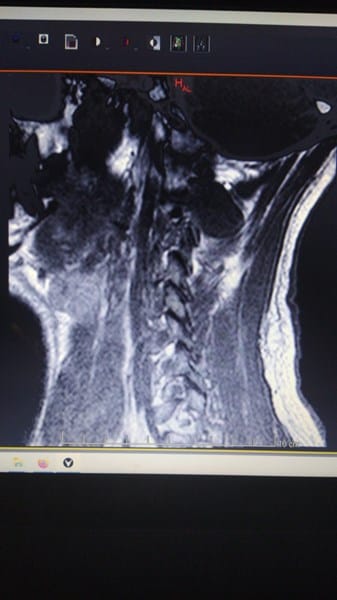

2/ Resonancia Magnética

Donde aparece espondiloartrosis con esclerosis de plataformas vertebrales y bordes ostofiticos

Osteartrosis en las articulaciones unciformes e interapofisiarias posteriores.

Discatrosis con baja señal de intensidad discal en secuencia T2

A nivel C3-4 Abombamiento discal paracentral y foraminal izquierdo

A nivel C4-5 Abombamiento discal con leve compromiso bilateral

A nivel C5-C6-C7 importantes abombamientos discales con compromiso bilateral-

Adjunto fotografias de la resonancia.